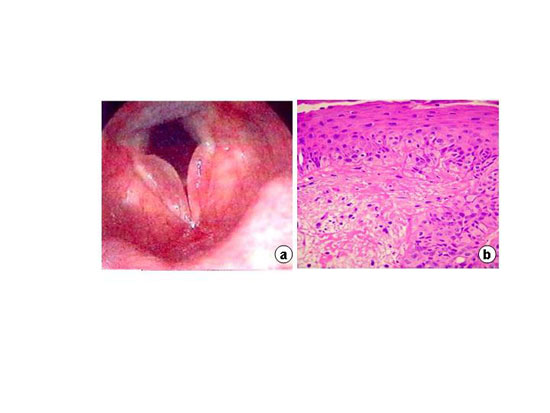

Paciente A.M.F., 51 anos, brasileira, sexo feminino, compareceu em consulta ambulatorial queixando-se de disfonia persistente, de evolução lentamente progressiva há três anos. Referia ser tabagista desde a juventude (32 anos/maço) e apresentava também sintomas de pigarro e queimação retroesternal. Estava em uso de omeprazol 40mg/dia e motilium há dois meses por diagnóstico de doença do refluxo gastroesofágico. A paciente apresentava voz rouca, áspera, grave e virilizada. Ao exame de videolaringoscopia, observou-se edema de Reinke volumoso, bilateral (Figura 1a), sendo que, em prega vocal direita, havia pequena placa leucoplásica na borda livre da franja edematosa.

A paciente foi submetida a microfonocirurgia, sendo que a análise hiostopatológica evidenciou edema de Reinke e presença de carcinoma espinocelular microinvasivo (Figura 1b), com margens cirúrgicas livres do comprometimento neoplásico. A paciente evoluiu com melhora progressiva das qualidades vocais, sendo orientada e estimulada a abandonar o vício do tabagismo e a realizar acompanhamento ambulatorial e endoscópico em nosso serviço.

Em a - exame endoscópico de edema de Reinke bilateral. Em b - carcinoma espinocelular microinvasivo, infiltrando a membrana basal (HE-40X- microsocpia de luz).